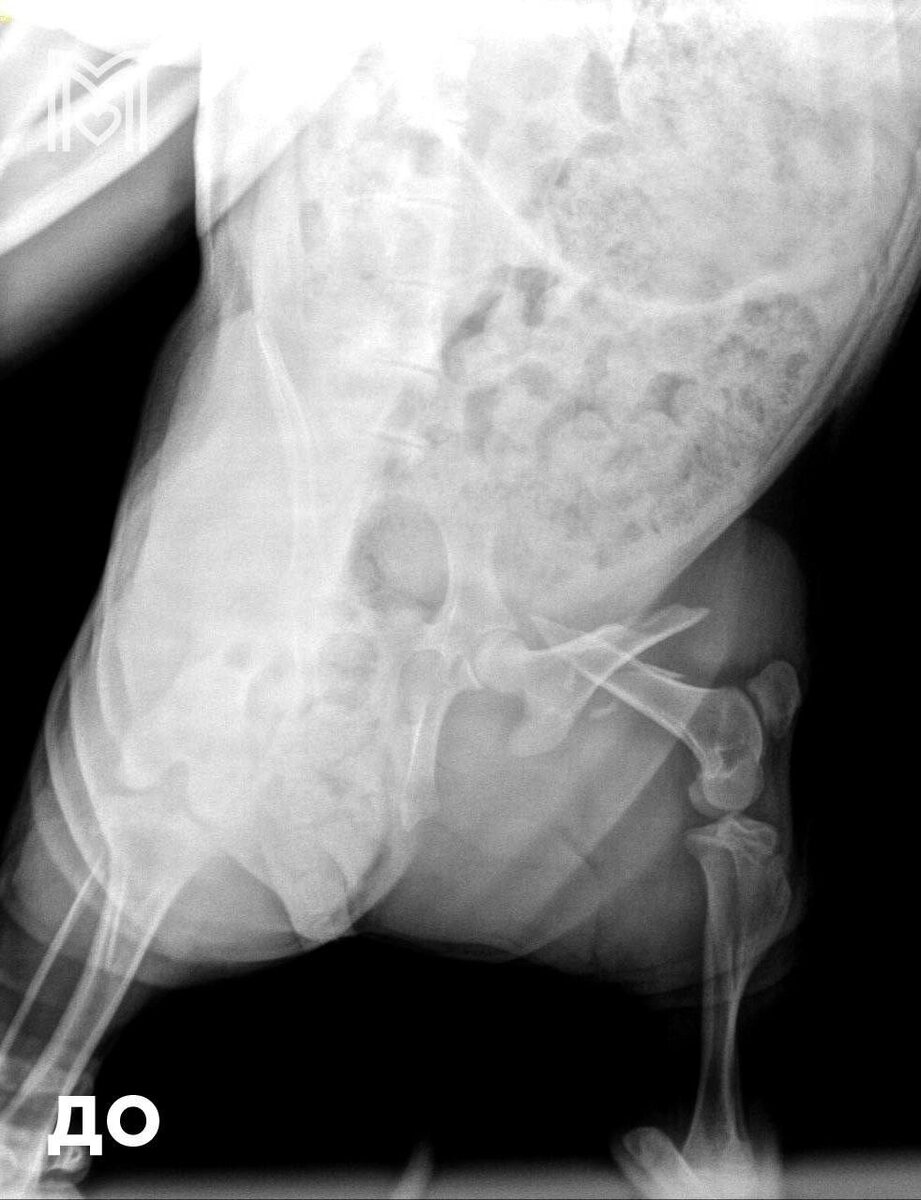

Π‘Π²ΠΈΠ½ΠΊΠ° ΠΏΠΎΠΏΠ°Π»Π° Π² ΠšΡƒΠ½Ρ†Π΅Π²ΡΠΊΡƒΡŽ Π²Π΅Ρ‚ΠΊΠ»ΠΈΠ½ΠΈΠΊΡƒ с Ρ…Ρ€ΠΎΠΌΠΎΡ‚ΠΎΠΉ β€” Π΅ΠΉ диагностировали ΠΏΠ΅Ρ€Π΅Π»ΠΎΠΌ, ΠΏΡ€ΠΈΡˆΠ»ΠΎΡΡŒ Π΄Π΅Π»Π°Ρ‚ΡŒ ΠΎΠΏΠ΅Ρ€Π°Ρ†ΠΈΡŽ.

Элвису соСдинили ΠΊΠΎΡΡ‚ΡŒ с ΠΏΠΎΠΌΠΎΡ‰ΡŒΡŽ мСталлоконструкции, ΠΎΠ½ Ρ…ΠΎΡ€ΠΎΡˆΠΎ пСрСнёс Π²ΠΌΠ΅ΡˆΠ°Ρ‚Π΅Π»ΡŒΡΡ‚Π²ΠΎ ΠΈ послС Π½Π°Ρ€ΠΊΠΎΠ·Π° отправился Π΄ΠΎΠΌΠΎΠΉ.